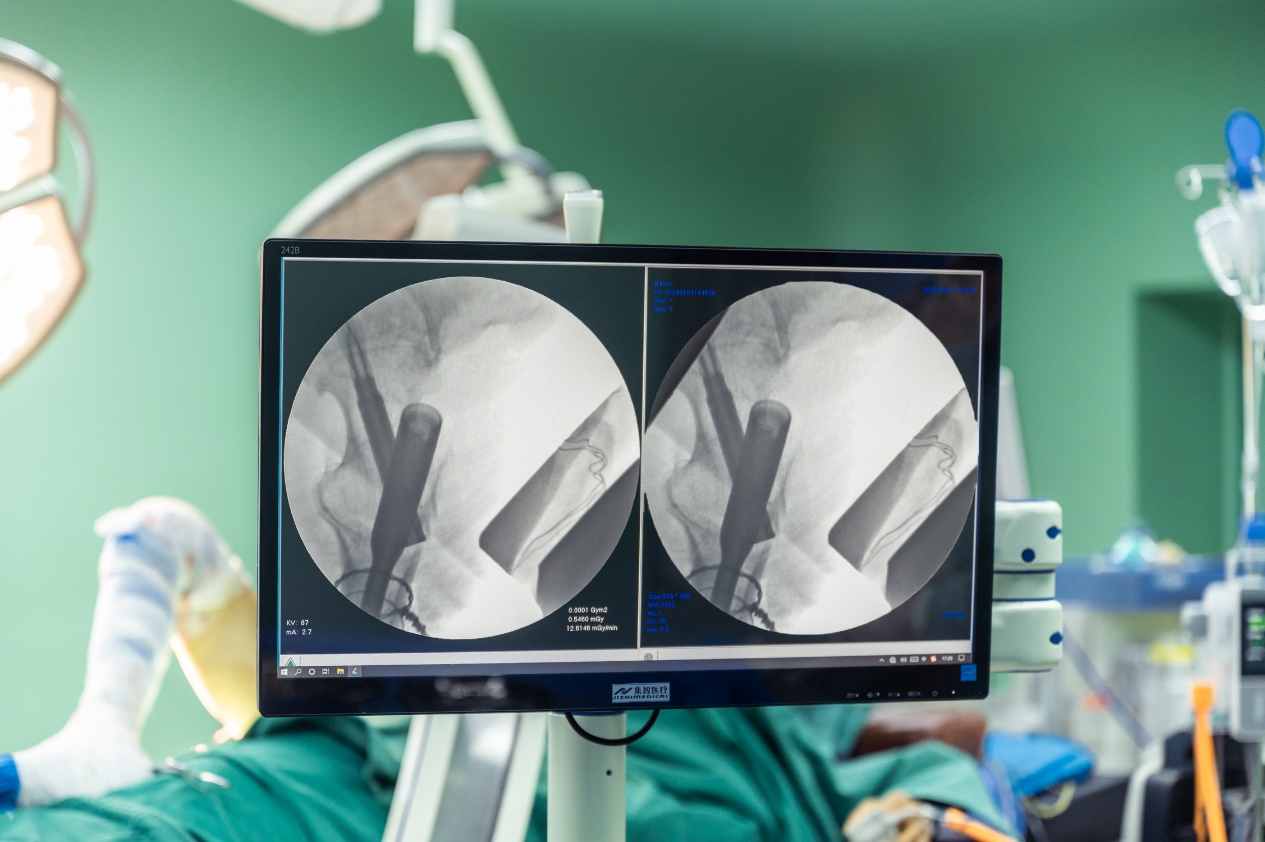

5.透视复位,观察复位情况

6.调节牵引力与方向,X线透视骨折短缩畸形纠正。